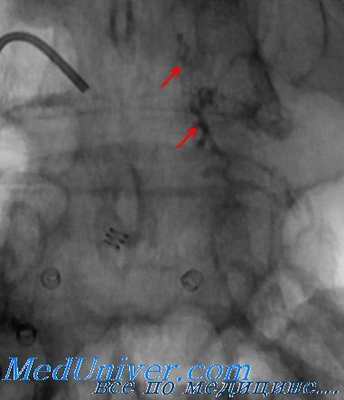

Ангиография проводится сразу после катетеризации артериального сосуда. Как правило, первой должна быть выполнена «струйная» аортография. При выявлении ранений крупных кровеносных сосудов таза специалист по ангиографии должен определить, какой именно сосуд поврежден. Следует помнить о возможности ретроперитонеального кровотечения в отдаленной от таза локализации. Наиболее типичным примером является комбинированный перелом таза и поясничного отдела позвоночника. При этом кровотечение бывает обусловлено повреждением поясничной артерии, что часто выявляется при проведении ангиографического исследования.

Если при аортографии повреждение артериального сосуда не установлено, следует продолжить исследование методом селективной ангиографии. Механизм травмы и модель перелома позволяют предположить повреждение внутренней подвздошной артерии, и изображение именно этого сосуда должно быть получено в первую очередь. Прежде, чем завершить исследование, следует получить изображение всего сосудистого русла таза по причине возможного обнаружения нескольких источников кровотечения. По некоторым данным, в 57% выявленных повреждений сосудов, имели место кровотечения разной локализации.